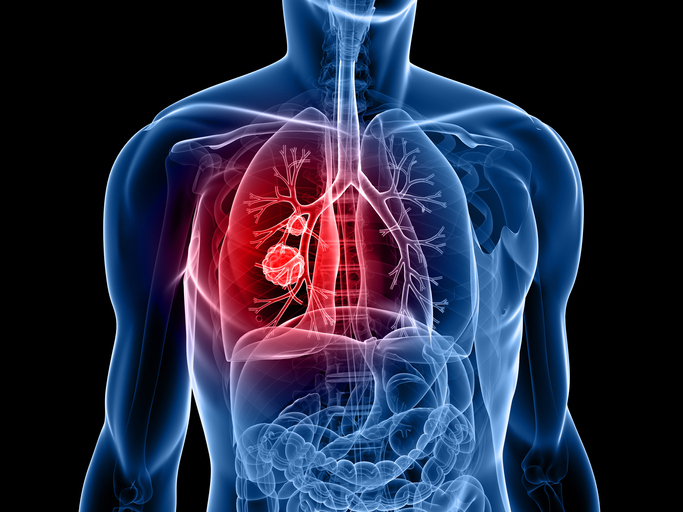

폐암은 폐에 비정상적인 암세포가 증식하여 덩어리를 형성하고 인체에 해를 미치는 것을 말합니다. 즉 폐에 생긴 악성종양을 말하며 폐 자체에 암이 발생하거나 다른 장기에서 생긴 암이 폐로 전이되어 발생합니다.

폐암 발병률과 폐암 사망률은 지속적으로 증가하고 있으며 폐암 진단을 받고 5년 이내 사망률은 86%나 된다고 합니다. 폐암은 재발이나 전이가 많고 완치율이 낮은 암입니다. 다른 암에 비해 사망률이 높습니다.